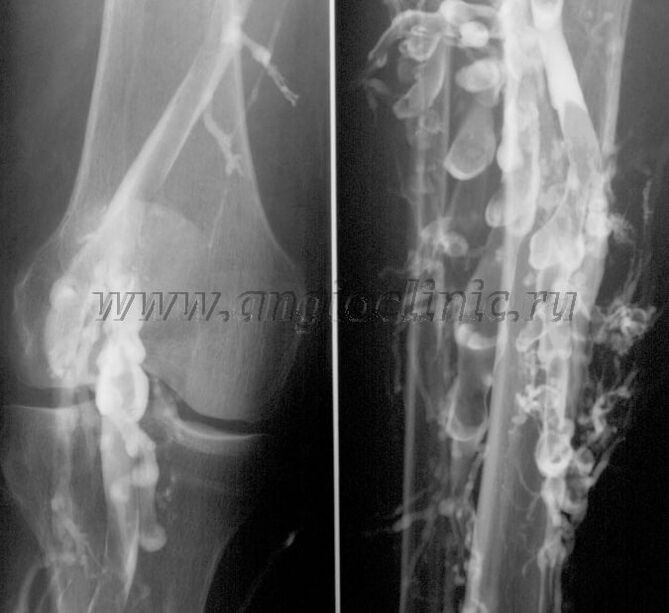

Contrast venography

Karaniwan, ang pag-scan ng ultrasound ay sapat na para sa isang buong pagsusuri ng venous pathology, ngunit sa ilang mga kaso kinakailangan na pag-aralan ang relasyon sa pagitan ng estado ng malalim at mababaw na venous system, lalo na sa kaso ng mga relapses ng varicose veins at pangalawang varicose veins.

Pag-scan sa ultratunog

Upang malutas ang mga problemang ito, ginagamit ang contrast X-ray na pagsusuri. Ang saphenous veins ay nabutas at ang contrast ay ibinibigay. Ang paggalaw ng kaibahan ay sinusunod sa monitor ng X-ray machine, at ang lahat ng kinakailangang mga pagsubok at projection ay isinasagawa. Sa kasalukuyan, ang venography para sa varicose veins ay bihirang ginagamit.